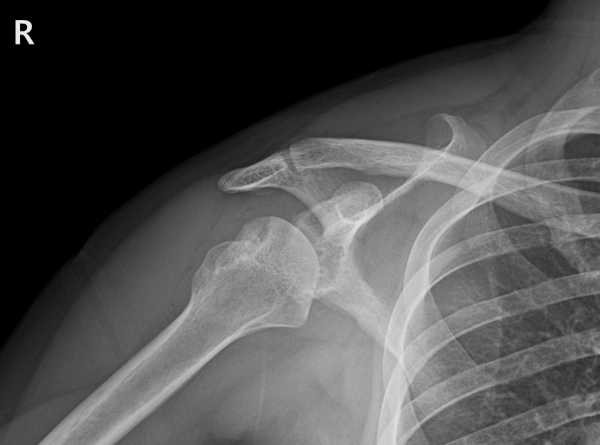

본원에 내원하여 검사를 진행했을 때 다음과 같은 소견을 확인했습니다.

재파열된 전하방 관절와순파열(Bankart) 병변(Recurrent Bankart lesion-재발성 전하방 관절와순파열)

매우 깊고 넓은 상완골두 후외측 골결손(Hill-Sachs) 결손(huge Hill-Sachs lesion-거대 상완골두 후외측 골결손)

상완골두 변형 및 결손

부분층 회전근개 파열

이 정도면 단순한 재탈구 수준을 넘어, 어깨 관절의 안정성이 거의 상실된 상태였습니다.